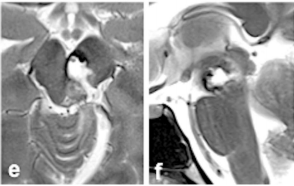

巴教授仅剔除部分头发,为她保留了美丽的长发。最终顺利全切海绵状血管瘤,术后轴向(e)和矢状(f)MRI证实病灶完全切除。

尽管出现了暂时性动眼神经麻痹,但在几周内就逐渐恢复,未留下任何神经功能缺损。更令人振奋的是,爱丽丝不仅重获健康,更重新踏上了马拉松赛道,用奔跑诠释着生命的韧性。